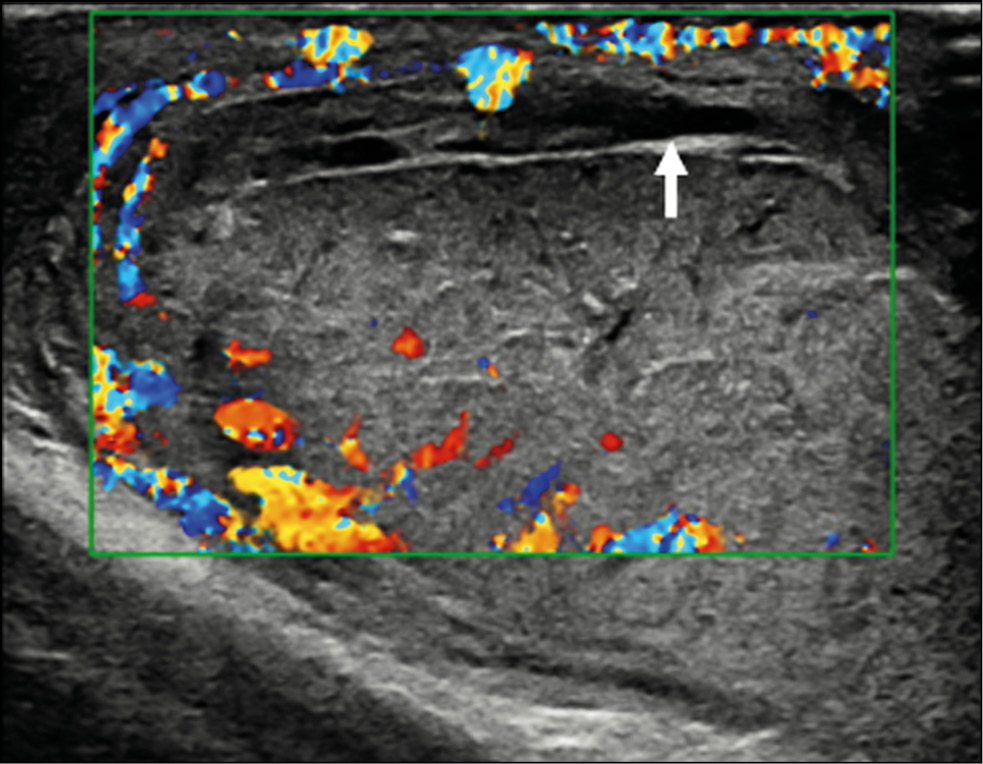

A healthy 15-year-old male teen was hit in the scrotum with a kick in the groin during a football match. He had an immediate and severe pain. After a few hours, although symptoms had improved, he presented to our emergency department with persistent swelling and purplish discoloration of the left scrotum. He did not report any other injuries. The genitourinary examination revealed that the left hemiscrotum was about two times larger than the right with severe ecchymosis. The left testicle was difficult to palpate because of pain and swelling, whereas the right testicle had a normal size and did not reveal any palpable abnormalities. The cremasteric reflex was not elicited on the left side. Scrotal ultrasonography (US) showed moderate scrotal edema and hematocele with a discontinuity in the tunica albuginea characterized by an abnormal contour (Figure 1). Color Doppler US (CDUS) documented a loss of vascularization in the upper pole that extruded into the broken portion of the testicle of approximately 2.5 cm (Figure 2) but no evidence of torsion or infarction. Urology consultation was requested, and a contrast-enhanced US (CEUS) was performed, which confirmed the diagnosis of testicular rupture and determined the amount of the vital parenchyma (Figure 3). The patient was hospitalized for urgent examination of the left hemiscotum based on the US results. During surgery, a large hematocele was evacuated, and a closer inspection of the testicle revealed a lesion of the tunica albuginea. Primary closure of the tunica was performed (Figure 4). The patient made an uneventful recovery, and he was discharged after 4 days.

Figure 3. Contrast-enhanced ultrasonography image determines the extent of vital parenchyma, helping in the preoperative decision-making process, and allows the recovery of vital testicular tissue, avoiding the need for orchidectomy.

The differential diagnosis of scrotal lesions includes epididymitis, orchitis, incarcerated inguinal hernia, testicular infarction, testicular fracture or rupture, testicular torsion, appendicular torsion, dislocated testicles, hydrocele, or hematocele [10]. CDUS is the first-line imaging modality for studying traumatic pathology of the scrotum according to the guidelines of the European Association of Urology [11]. Thus, evaluating vascular perfusion and testicular integrity is important to distinguish testicular rupture from other lesions. Using modern ultrasonic equipment, sensitivity and specificity of 95%–100% are now possible for the diagnosis of testicular rupture [12]. The normal tunica albuginea appears as a thin hypoechoic line surrounding the testicular parenchyma. It can be difficult to appreciate it in the presence of hematocele. The regularity of the testicular contour should be checked in addition to the integrity of the tunica albuginea. Essentially, when testicular rupture occurs, the testicle loses its normal oval morphology because of parenchymal extrusion [13]. Thus, the irregularity of the testicle’s morphology is an indirect sign of ruptured tunica albuginea. Additional US findings include heterogeneous echotexture, rupture of the vaginal tunic, fracture lines through the testicle, decrease or loss of blood flow, scrotal thickening, and hematocele formation. CDUS is indispensable in the evaluation of a post-traumatic scrotum [14] since the rupture of the tunica albuginea is always associated with a rupture of the tunica vasculosa (composed of capsular arteries), resulting in a loss of the vascular signal of the underlying parenchyma. This aspect is extremely important because it can help determine the viability of the testicular parenchyma [15]. However, CDUS can be equivocal in acute cases because it may not detect low-flow states, particularly in pediatric patients [16], and is considered unreliable in defining ischemia [17] that could cause a delay in appropriate surgical treatment. CEUS can be proposed in cases where conventional US diagnosis remains inconclusive. CEUS is very sensitive to reveal the parenchymal vascularity and its changes in the damaged testicle [18]. The official guidelines of the European Federation of Societies for Ultrasound in Medicine and Biology describe the usefulness of CEUS in many areas [19]. Usually, 4.8 mL of SonoVue™ (Bracco Spa, Milan) is used. Contrast agents for CEUS examination are not nephrotoxic, the phospholipidic shell is metabolized by the liver, and the sulfur hexafluoride gaseous component is exhaled through the lungs. The technique can be performed in patients with kidney failure and does not require previous laboratory tests. In addition, ultrasonic contrast agents (UCAs) have a lower risk of adverse reactions than contrast agents commonly used in computed tomography and magnetic resonance imaging. The CEUS is also inexpensive, fast, portable, repeatable, and safe with multiple injections, all without radiation exposure [20]. The arterial phase in CEUS is the most important tool of the examination. The testicle and epididymis enhance quickly, but it can vary from individual to individual. Arteries enhance first, followed in seconds by the reinforcement of the entire parenchyma. The scrotal wall tends to enhance lesser than the content. The enhancement decreases in a variable period usually 3 min. The normal testicular parenchyma is homogeneous with an echogenic surface line indicating the tunica albuginea. On CEUS, the testicle should enhance homogeneously with a striated pattern representing UCAs within the normal intratesticular vascular anatomy [20]. CEUS more clearly depicts the fracture lines, interruption of the tunica albuginea, and both intratesticular and extratesticular hematomas [21]. It can assess exact extent of viable testis, allowing the urologist to decide when the partial salvage of the organ is a good solution [22]. In addition, small testicular tumors may appear avascular in CDUS; thus, the differentiation of infarction can be difficult. CEUS can distinguish vascularized from non-vascularized focal testicular lesions, which help exclude malignancy. Finally, the Scrotal and Penile Imaging Working Group of the European Society of Urogenital Radiology provided position statements with the aim of guiding the use of imaging, especially multiparametric US, in scrotal trauma. Accordingly, CEUS can be used to identify the presence or absence of flow when CDUS is not diagnostic; identify testicular ruptures, fracture lines, hematomas, and ischemic changes in equivocal cases in conventional US; and distinguish between avascular and poorly vascularized lesions, to differentiate hematomas from tumors [23].